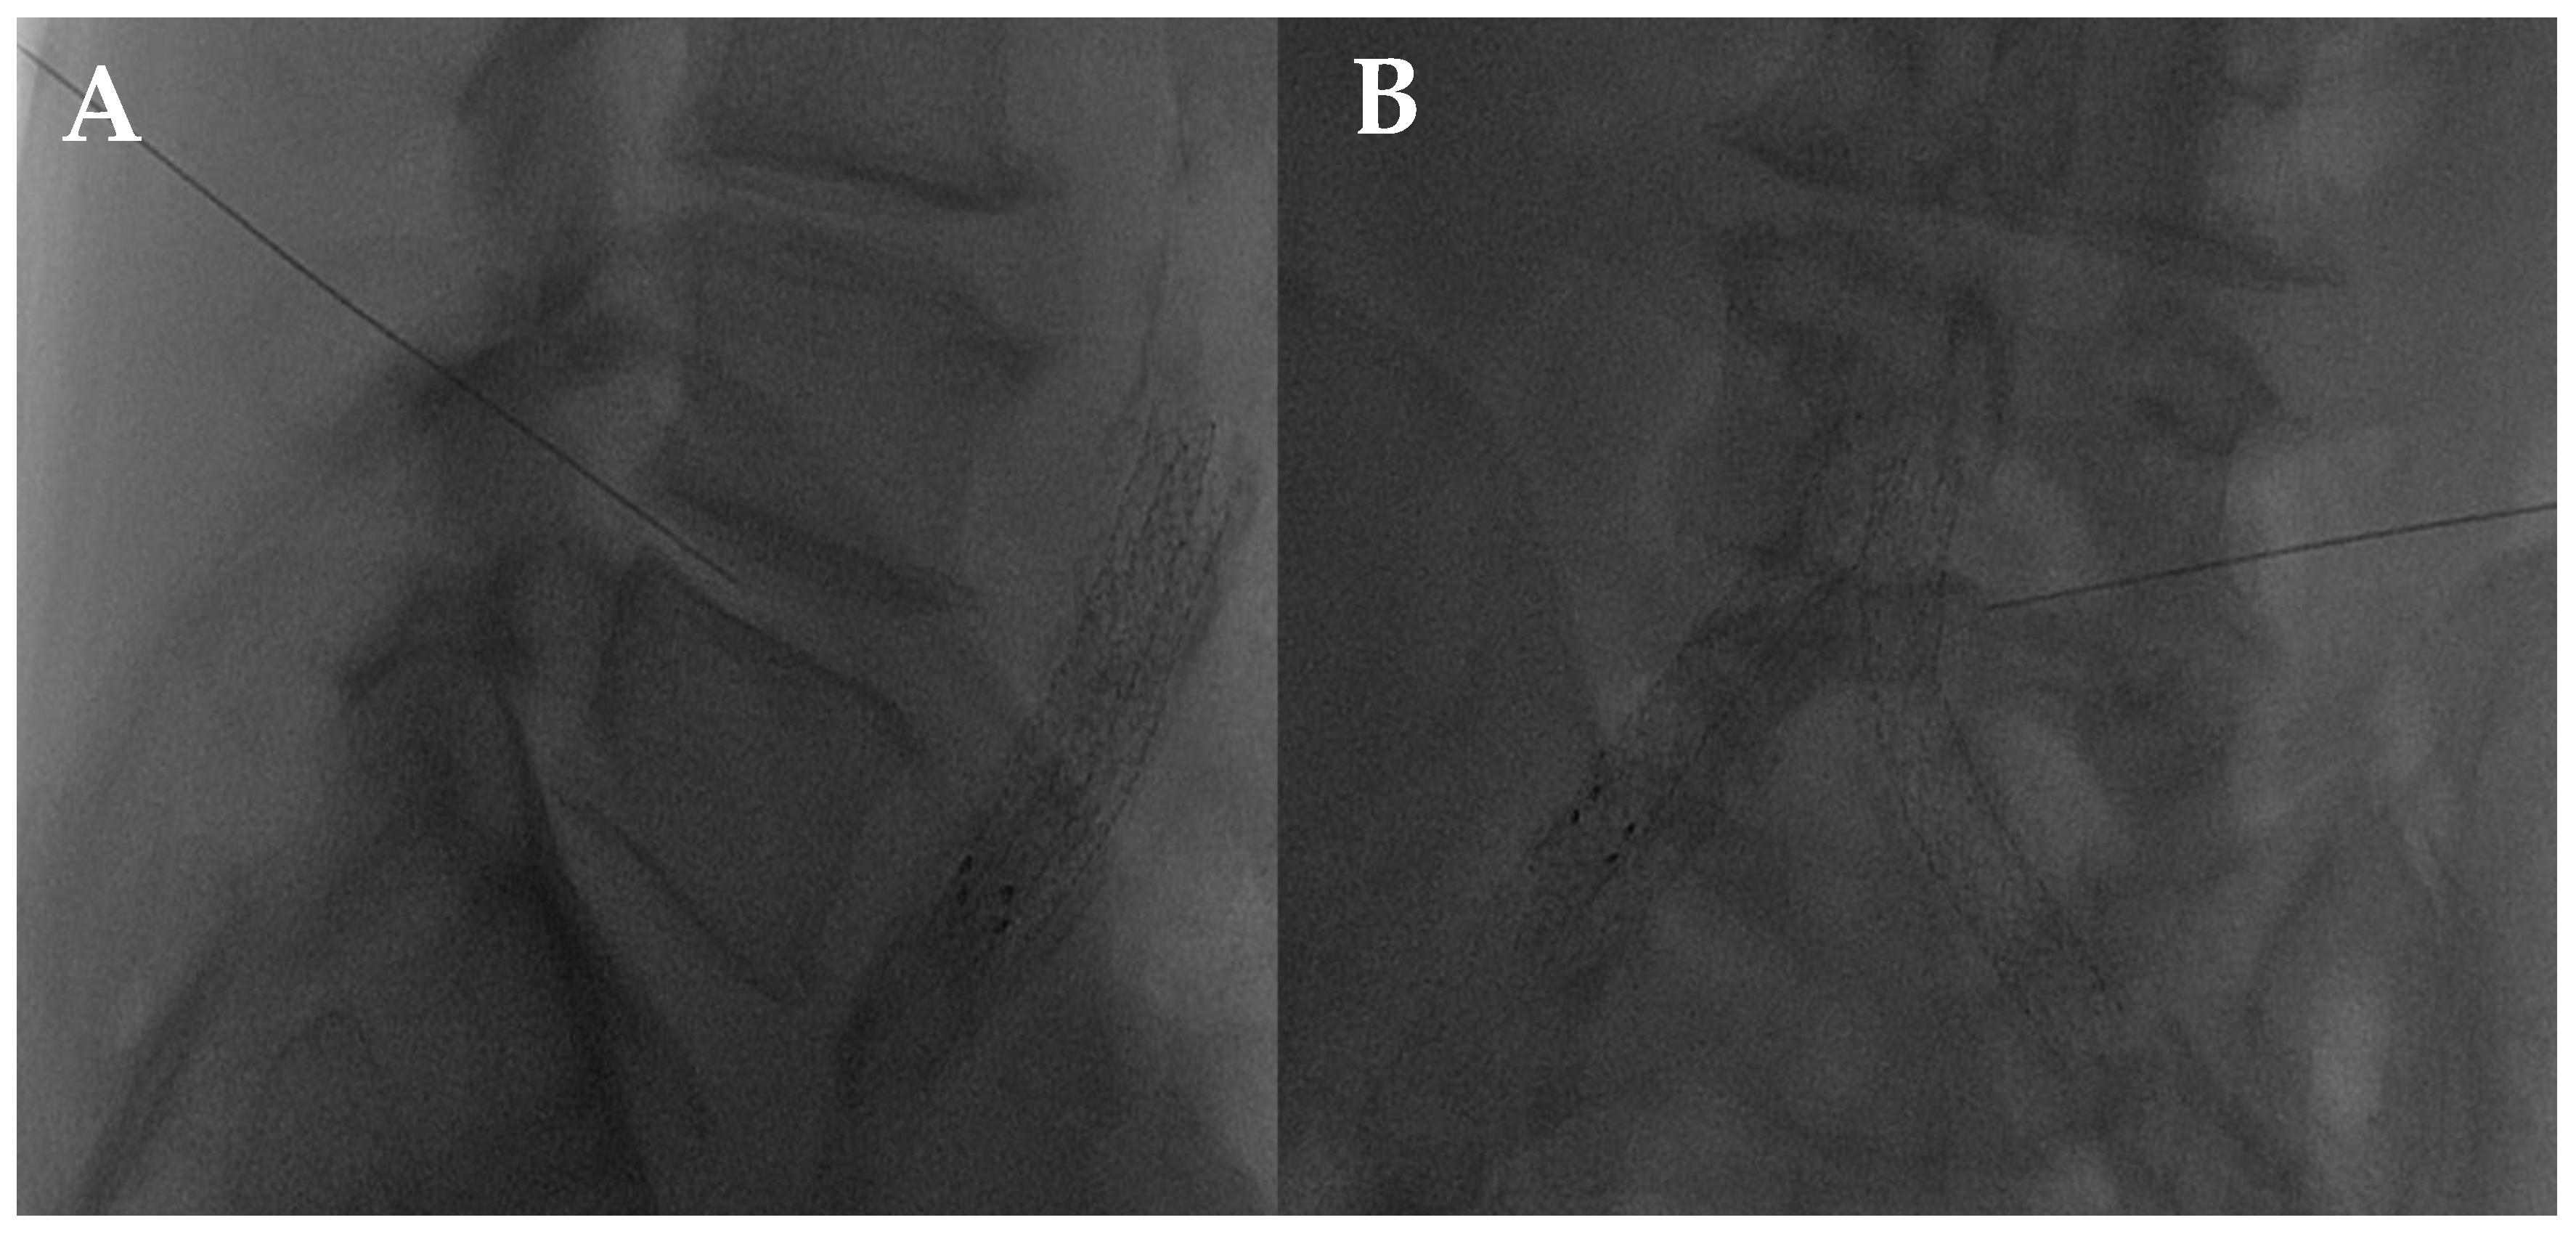

- Amoretti, N.; Amoretti, M.-E.; Hovorka, I.; Hauger, O.; Boileau, P.; Huwart, L. Percutaneous Facet Screw Fixation of Lumbar Spine with CT and Fluoroscopic Guidance: A Feasibility Study. Radiology 2013, 268, 548–555. [Google Scholar] [CrossRef]